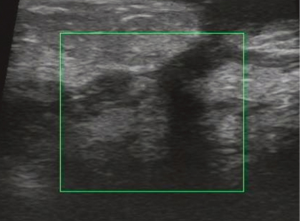

All of 178 patients had breast mass with unclear boundaries, ranging from 2~14 cm in diameter. Of them, 134 patients (75.3%) complained of skin ulcerations and swelling (Figure 1), 127 (71.3%) with abscesses (Figure 2), 18 (10.1%) with peau d’orange sign, which was easily confused with breast cancer (Figure 3), 6 (3.4%) with skin erythema on legs.

USG showed ill-defined, hypoechoic, heterogeneous lesions in most of the patients with GLM. Sometimes the breast lesion had specific signs including ‘Funnel sign’, ‘tunnel sign’ or ‘quicksand sign’, while it complicated with abscesses (Figures 4-6). According to the previous experience (5,11), 26 patients underwent mammography in our early study, which did not show characteristic signs of the lesion. In late study, patients did not had mammography as a routine examination because of its limitations such as the aggravation of the pain after mammography.